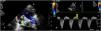

A 10-day-old term neonate with tachypnea and peripheral oxygen saturation of 90% was referred to us with a diagnosis of transposition of the great arteries with intact ventricular septum for early arterial switch operation. The child weighed 2.8 kg and was not dysmorphic. Precordial examination revealed cardiomegaly, loud second sound and a grade 2 mid-systolic murmur in the upper left sternal border. Clinical examination and transthoracic echocardiography suggested usual arrangement of the visceroatrial structures and normal leftward cardiac apex. Systemic and pulmonary venous drainage were normal. A stretched open foramen ovale shunted right-to-left. The atrioventricular relationship was concordant. The parasternal long-axis view showed intact interventricular septum, good left ventricular function and a bifurcating great artery arising from the left ventricle (Figure 1 and Video 1). The great artery relationship was noted to be normal with an unobstructed anterior and leftward located main pulmonary artery. The right pulmonary artery was not seen to arise from the main pulmonary artery, unlike the left pulmonary artery (Figure 2a). The anomalous origin of the right pulmonary artery from the ascending aorta gave the appearance of bifurcation. Pan-diastolic flow reversal in the descending aorta was confirmative of the aortic runoff (Figure 2b). The arterial duct was not patent. The right ventricle was dilated and dysfunctional. The estimated left pulmonary artery systolic pressure was 105 mmHg from the tricuspid regurgitation jet.

Transthoracic two-dimensional echocardiography cine loop, parasternal long-axis projection, with color comparison, showing the bifurcating great artery arising from the left ventricle (white asterisk: aorta, yellow asterisk: right pulmonary artery). LA: left atrium; LV: left ventricle; RV: right ventricle.